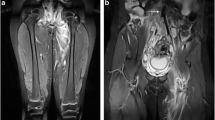

Duplex sonography of the right limb showed an epifascial thrombophlebitis that barely reached the crossing veins without deep venous thrombosis. A pulmonary embolism was ruled out by a CT-Angiography of the chest. The additional computer tomography of the abdomen and pelvis revealed an abnormal inferior caval vein which was fed just by the hepatic veins. The blood of the extremities and the kidneys was drained over a varicose venous plexus equivalent to the thoracic venae azygos and hemiazygos. In the sense of a bypass circulation the umbilical vein was recanalized, and varicose veins of the abdominal wall were apparent (Fig. 1). The superficial femoral vein on the left side was filled by a probably old thrombus which reached the varicose network in the pelvis (Fig. 2). The right kidney was atrophic (Figs. 1, 3). We diagnosed an epifascial thrombophlebitis of the right leg with missing lower IVC and atrophic right kidney. The history of idiopathic deep vein thrombosis and the present thrombophlebitis could now be explained by the atresia of the inferior caval vein. It has been suggested that this anatomical situation contributes to a prothrombotic situation due to stasis of the blood for lack of sufficient drainage through the azygos and hemiazygos veins [14].